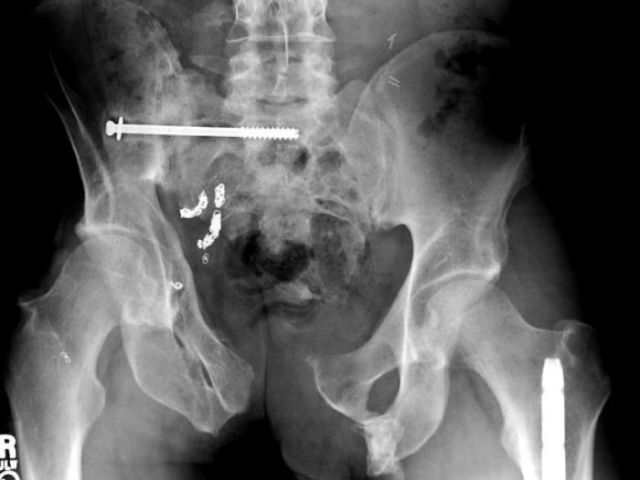

These x-rays will make you wonder how this could ever have happened in the first place.